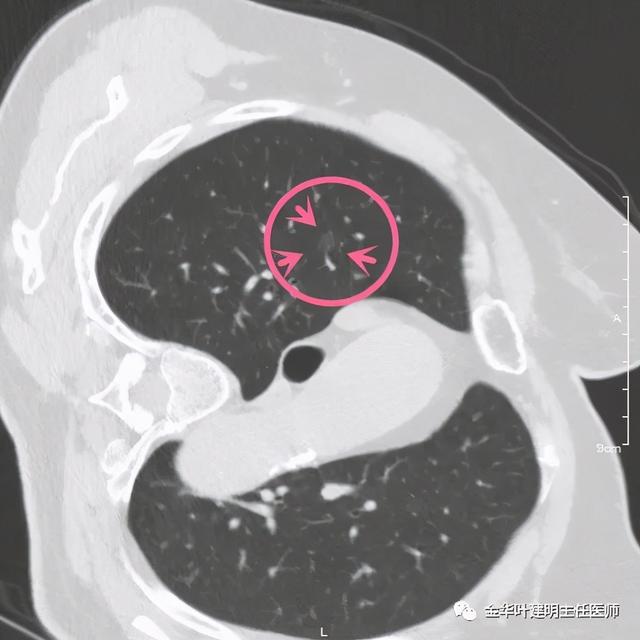

患者为女性 , 今年76岁 , 平时体质甚好 , 家务及地里劳动都胜任 , 头发仍乌黑(我自己倒有一半白发了) 。 肺功能与血气分析正常 。 CT检查图像如下:

可见右肺上叶混合磨玻璃结节 , 有明显分叶征 , 瘤肺边界虽然欠清楚 , 但轮廓比较清晰 。 看着也许会考虑炎性 , 但总觉得其比较僵硬 , 看去不舒服 。 这种病灶一是如果持续存在就极可能是肺癌 , 二是靶扫描显示更清晰的细节 , 如果瘤肺边界还是清楚的 , 也基本是肺癌 。 我们回顾发现其于2019年3月在我们医院做过CT平扫 , 当时报告如下: